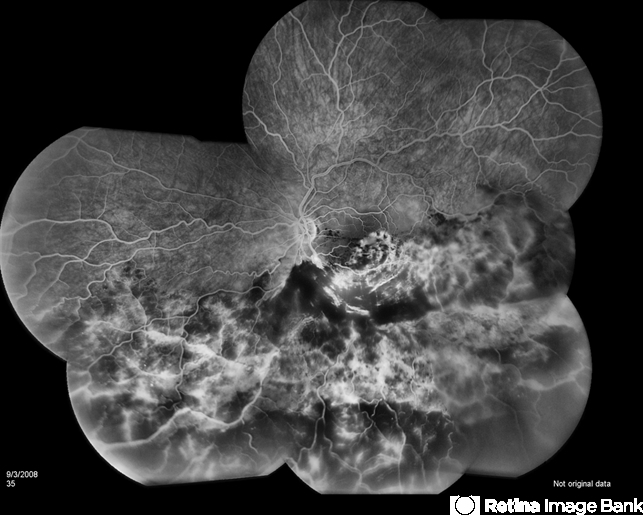

Excellent montage of this left eye's Hemivein Occlusion. It is unfortunate that it is so extensive, however, this captures the essence of well documented pan retinal photography.

By Brandon G. Busbee, MD

Tennessee Retina, PC - Uploaded on Dec 28, 2012.

- Alecia Camp, CRA - Tennessee Retina - Nashville, TN

- Fundus camera